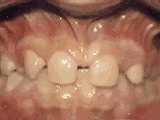

Incisivos laterales faltantes

Este paciente nació sin los incisivos laterales. Usó frenos por 20 meses para corregir la posición de los dientes. Posteriormente, los dientes faltantes fueron reemplazados con puentes fijos “Maryland”.